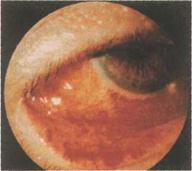

энтеровирус – 70, Коксаки А-24 боль в глазах, гиперемия, слезотечение, светобоязнь. Выраженный отек, сужение глазной щели. Незначительное слизисто-гнойное отделяемое. Кровоизлияние различной интенсивности. Могут быть мелкие фолликулы. инкубационный период 1-2 суток, длительность заболевания 2-3 недели